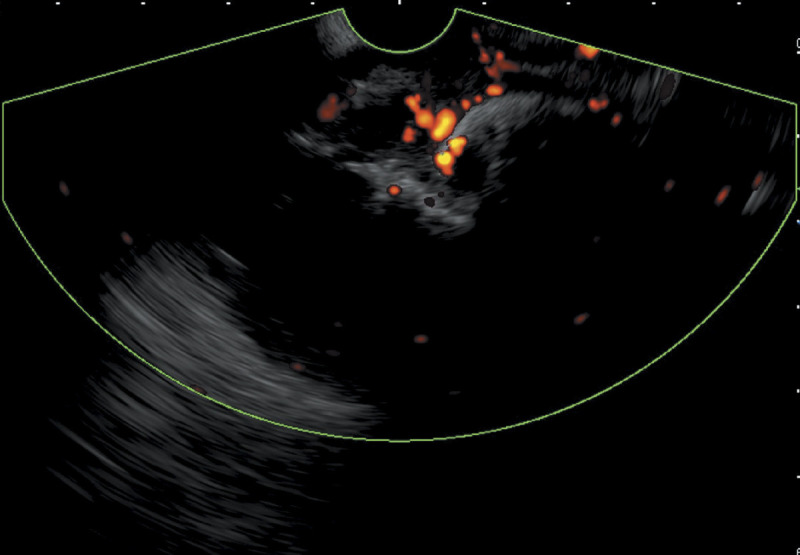

EUS-guided cyanoacrylate glue injection for the management of refractory bleeding from postglue ulcer following gastric varices treatment (with video).